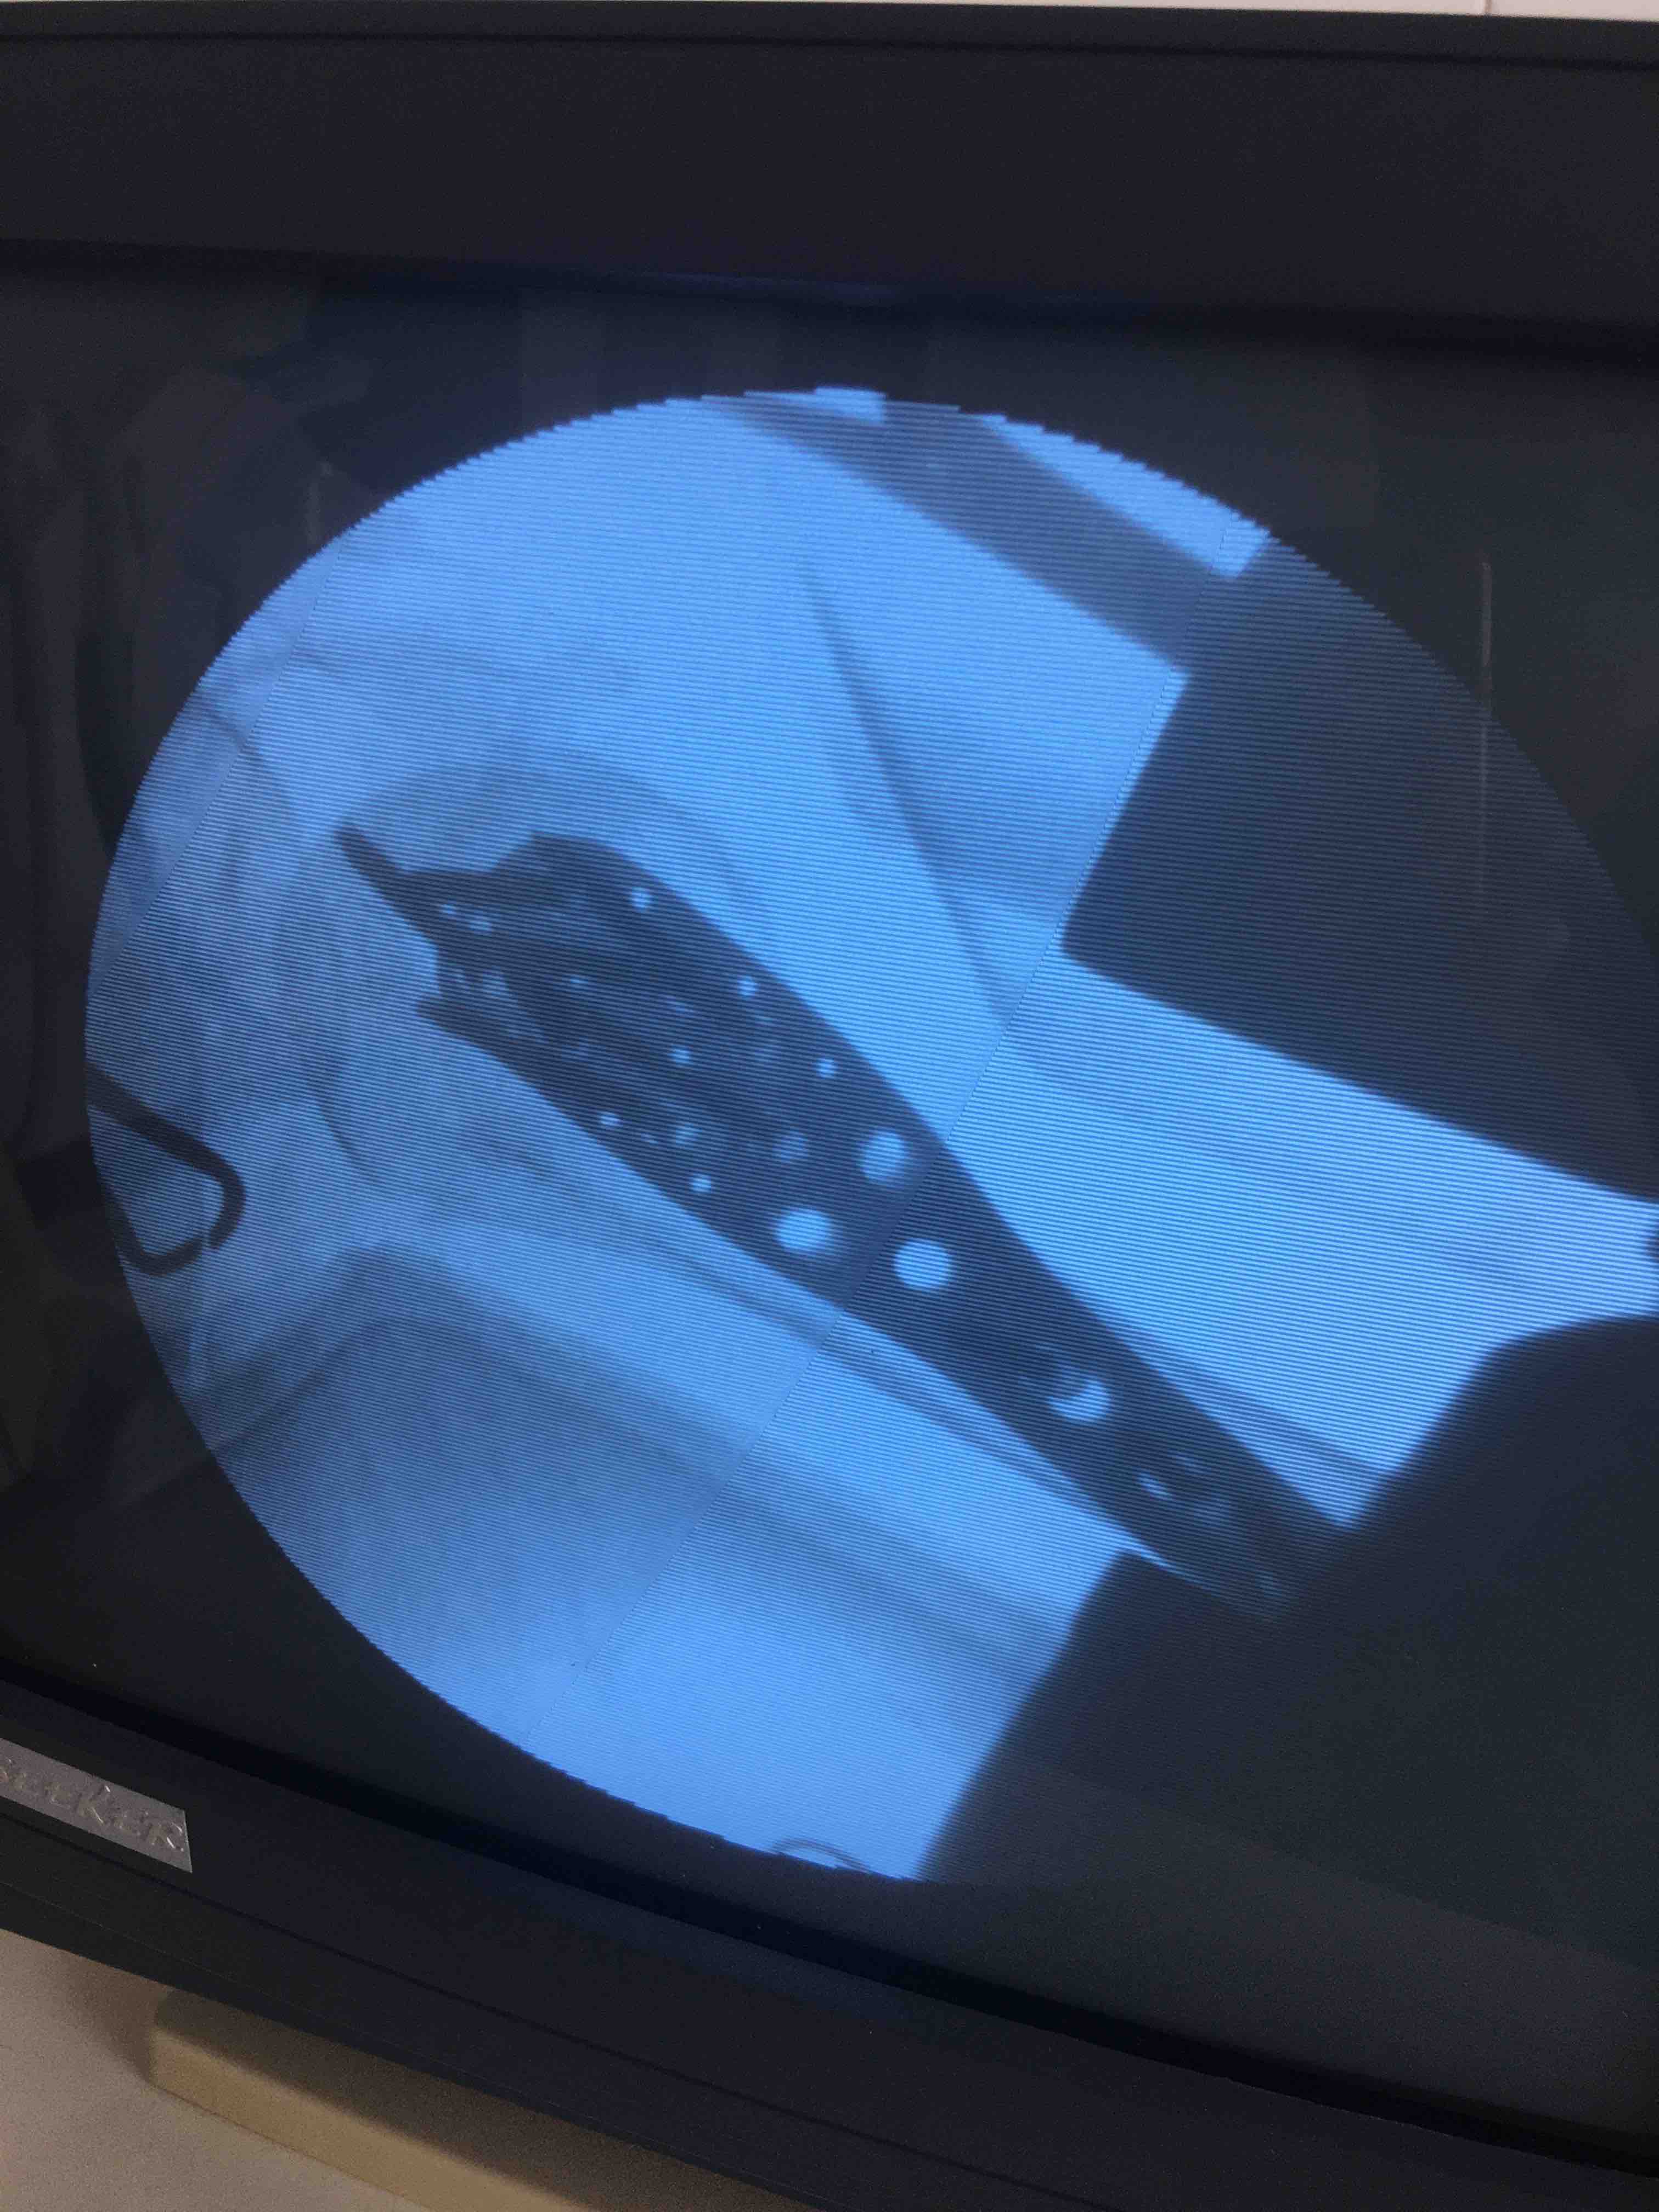

诊断右肱骨外科颈粉碎性骨折在臂丛麻醉下行切复内固定术,术后抗炎,消肿等处理。